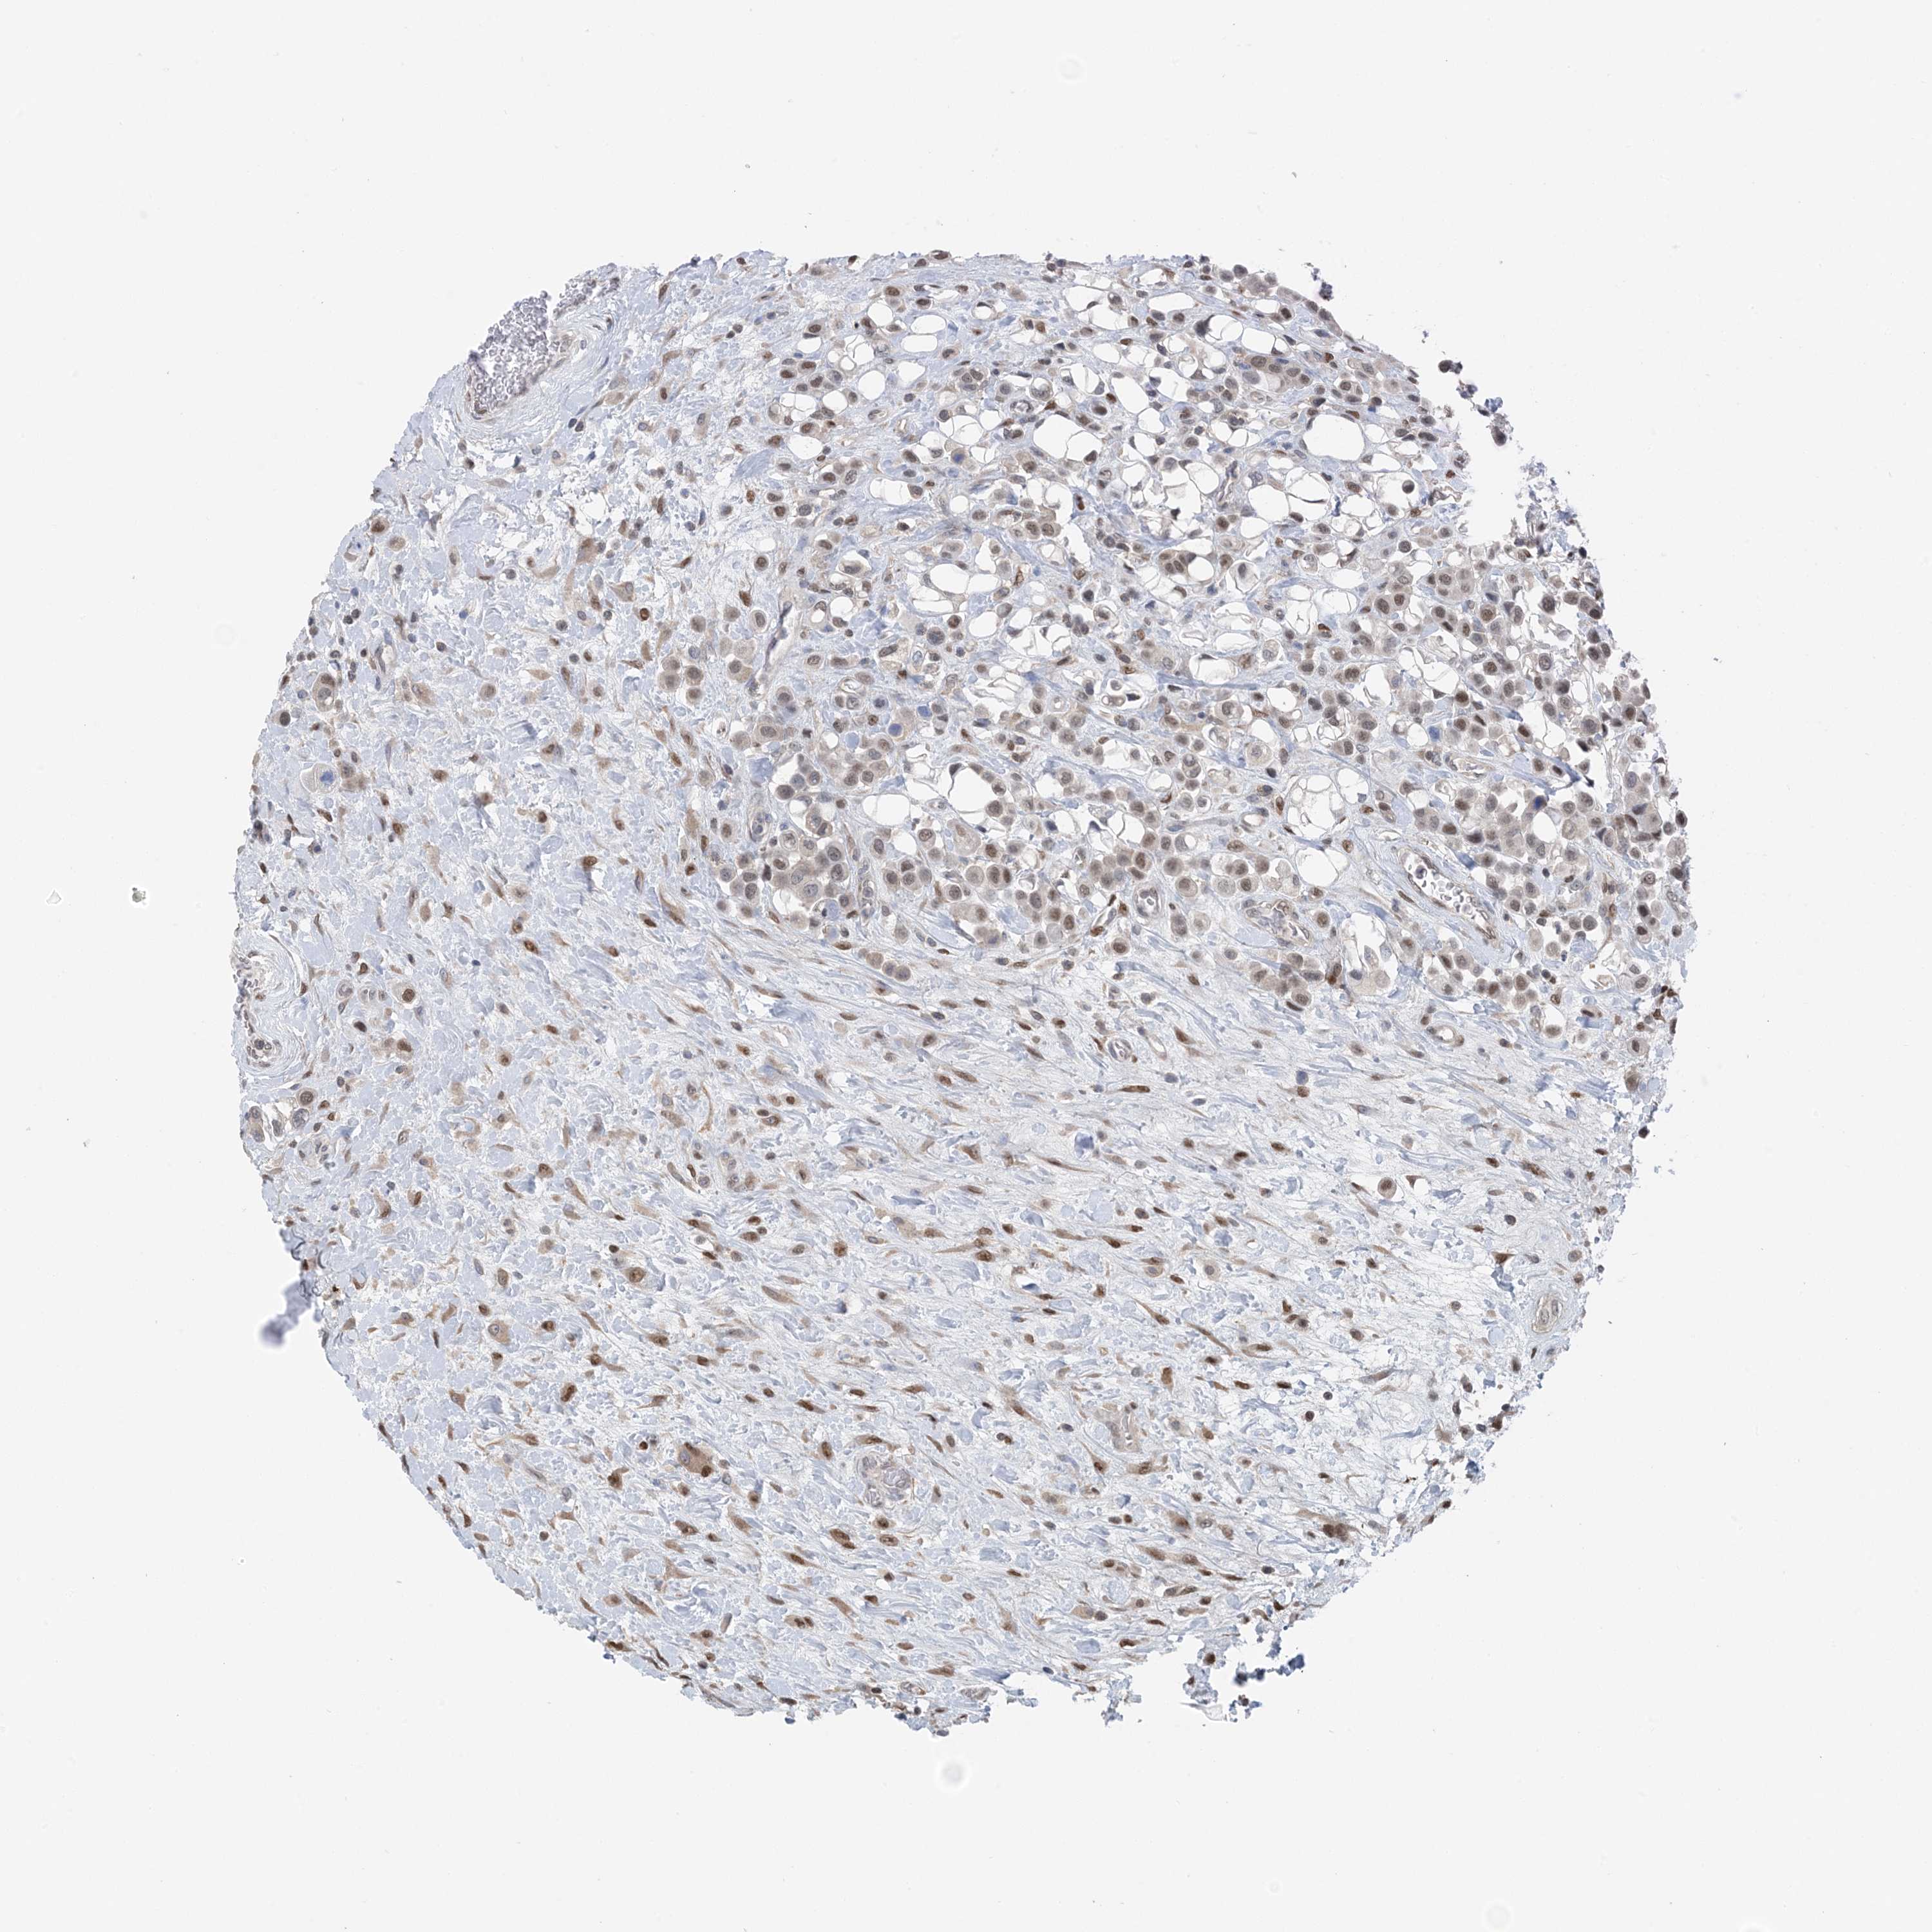

UROTHELIAL CANCER - Protein expressioni

A mouse-over function shows sample information and annotation data. Click on an image to view it in a full screen mode. Samples can be filtered based on level of antibody staining by selecting one or several of the following categories: high, medium, low and not detected. The assay and annotation is described here.

Note that samples used for immunohistochemistry by the Human Protein Atlas do not correspond to samples in the TCGA dataset.

Antibody stainingi

Antibody staining in the annotated cell types in the current human tissue is reported as not detected, low, medium, or high, based on conventional immunohistochemistry profiling in selected tissues. This score is based on the combination of the staining intensity and fraction of stained cells.

Each image is clickable and will lead to virtual microscopy that enables deeper exploration of all samples and also displays staining intensity scores, fraction scores and subcellular localization as well as patient and tissue information for each sample.

Antibody HPA035063

Antibody HPA035064

Urothelial carcinoma, High grade

Urothelial carcinoma, Low grade